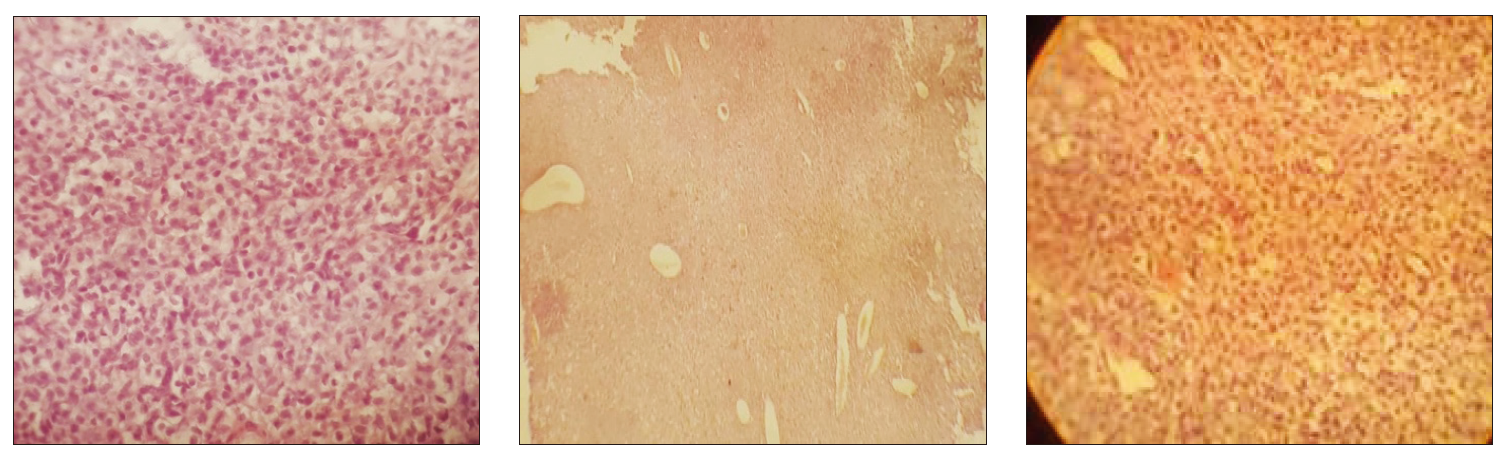

肿块切片可见一界限清晰的区域,由片状圆形至多边形组织细胞构成;细胞胞质中等量、淡嗜伊红,核圆或卵圆形、居中或偏位,染色质细点状,核仁不明显。病变周边常可见轻至中度小淋巴细胞浸润(图5)。

图5. 细胞具有中等量淡嗜酸性胞质,核圆或卵圆形,居中或偏位,染色质细点状,核仁不明显。

组织细胞瘤的细胞学特征通常包括圆形或多边形的组织细胞样细胞,胞浆丰富,核呈圆形或卵圆形,染色质细腻,核仁不明显。免疫组化染色可进一步确认其来源,常见标志物包括CD1a(朗格汉斯细胞)和CD11c(树突状细胞)。

细胞学检查未见恶性特征,组织活检最终确诊为良性组织细胞瘤。尽管该肿瘤在病理上为良性,但其巨大体积及对周围骨组织的侵袭性表现提示,在某些情况下,组织细胞瘤可能表现出“局部侵袭性”生长行为,尤其在老年犬中更易出现非典型表现。